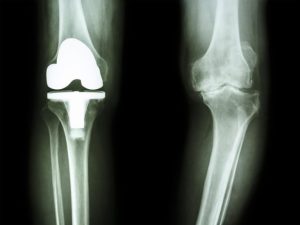

膝の手術では、人工関節という「異物」が体内に埋め込まれます。

この人工関節は、通常の組織よりも細菌が付着しやすく、一度感染が起きると非常に治りにくいのが特徴です。

これを「人工関節周囲感染症(PJI)」と呼びます。

放置するとこんなに怖い!「人工関節周囲感染症(PJI)」のリスク

人工関節周囲感染症(PJI)は、患者さんのQOL(生活の質)を著しく低下させる、非常に深刻な合併症です。

再手術が必要になる

抗生物質の長期投与が必要になる

最悪の場合、人工関節の除去や、患部の切断に至ることもある

PJIは、手術直後に発症する「早期感染」と、数年後、ときには10年以上経ってから発症する「後期感染」に分けられます。

早期感染は、手術時の不十分な感染対策などが原因となることが多いですが、後期感染の原因の一つに、「口腔内の細菌が血流に乗って運ばれること」が挙げられます。

つまり、手術後、何年も経ってから、「歯周病」が原因で人工関節が感染してしまう可能性があるということです。